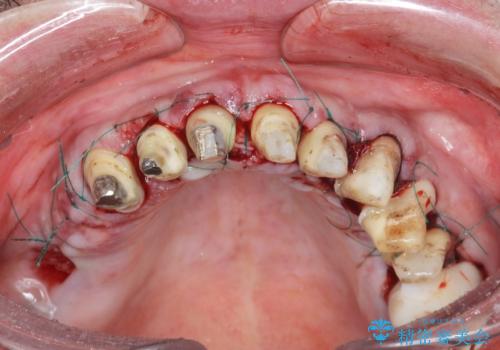

セラミッククラウンを除去し仮歯を装着し、歯周外科手術を行い歯ぐきの状態を改善したのち、適合の良いセラミッククラウンを再作製をする治療計画としました。

- 90.2万円(ジルコニアクラウン×6・仮歯×6 ・歯周外科手術)費用は治療当時の料金となります

- 外科手術のため、術後に出血、痛みや腫れ、違和感を伴います